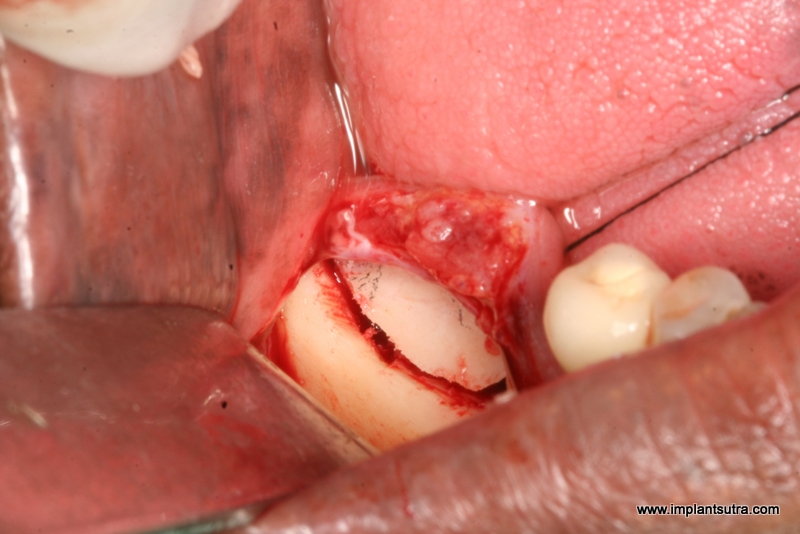

The "smile" osteotomy

Mobilising the the fragment vertically. Note that the coronal fragment is still pedicled to the lingual mucosa. The incision in the soft tissue is vestibular rather than crestal. One can use a bur, peizosurgery saw or oscillating saw for this cut..One can easily create a gap of 5 to 6mm or more using this technique.

Maintaining the gap with a graft: Here we have used a block of FDBA from the

Tata Tissue Bank in Mumbai. Alternatively one can use autograft harvested from the chin or ramus , or practically any kind of allograft or xenograft by itself or mixed with autograft. In case of particulate autograft it may be necessary to stabilise the coronal fragment with plates and screws. This may be needed even in case of block grafts if the fragments do not maintain position.